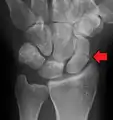

التشخيص

يتم عادة تشخيص كسر العظمة الزورقية بالتصوير بالأشعة السينية الجانبية, ولكن لا تظهر جميع الكسور في البداية ولذلك الناس اللذين يعانون من الم عند الضغط على منطقة السعوط يضعون جبيرة عصابة الإبهام من سبع إلى عشر أيام وحينها يتم اخذ مجموعة أخرى من صور الأشعة السينية.

وإذا كان هناك كسر شعري سيكون الشفاء واضحا, وحتى في ذلك الحين لن يكون كسر العظمة الزورقية واضحا, ويتم اخذ صورة بالأشعة المقطعية لتقيم العظمة الزورقية بوضوح أكبر, كما انه يفضل التصور بالرنين المغناطيسي إذا توفر عن التصوير بالأشعة المقطعية لأنه يمكن ان يعطي تشخيصا فوري. ويعد لا يظهر التصوير الملون طريقة فعالة لتشخيص الكسر الذي في صور الأشعة السينية.

معرض صور